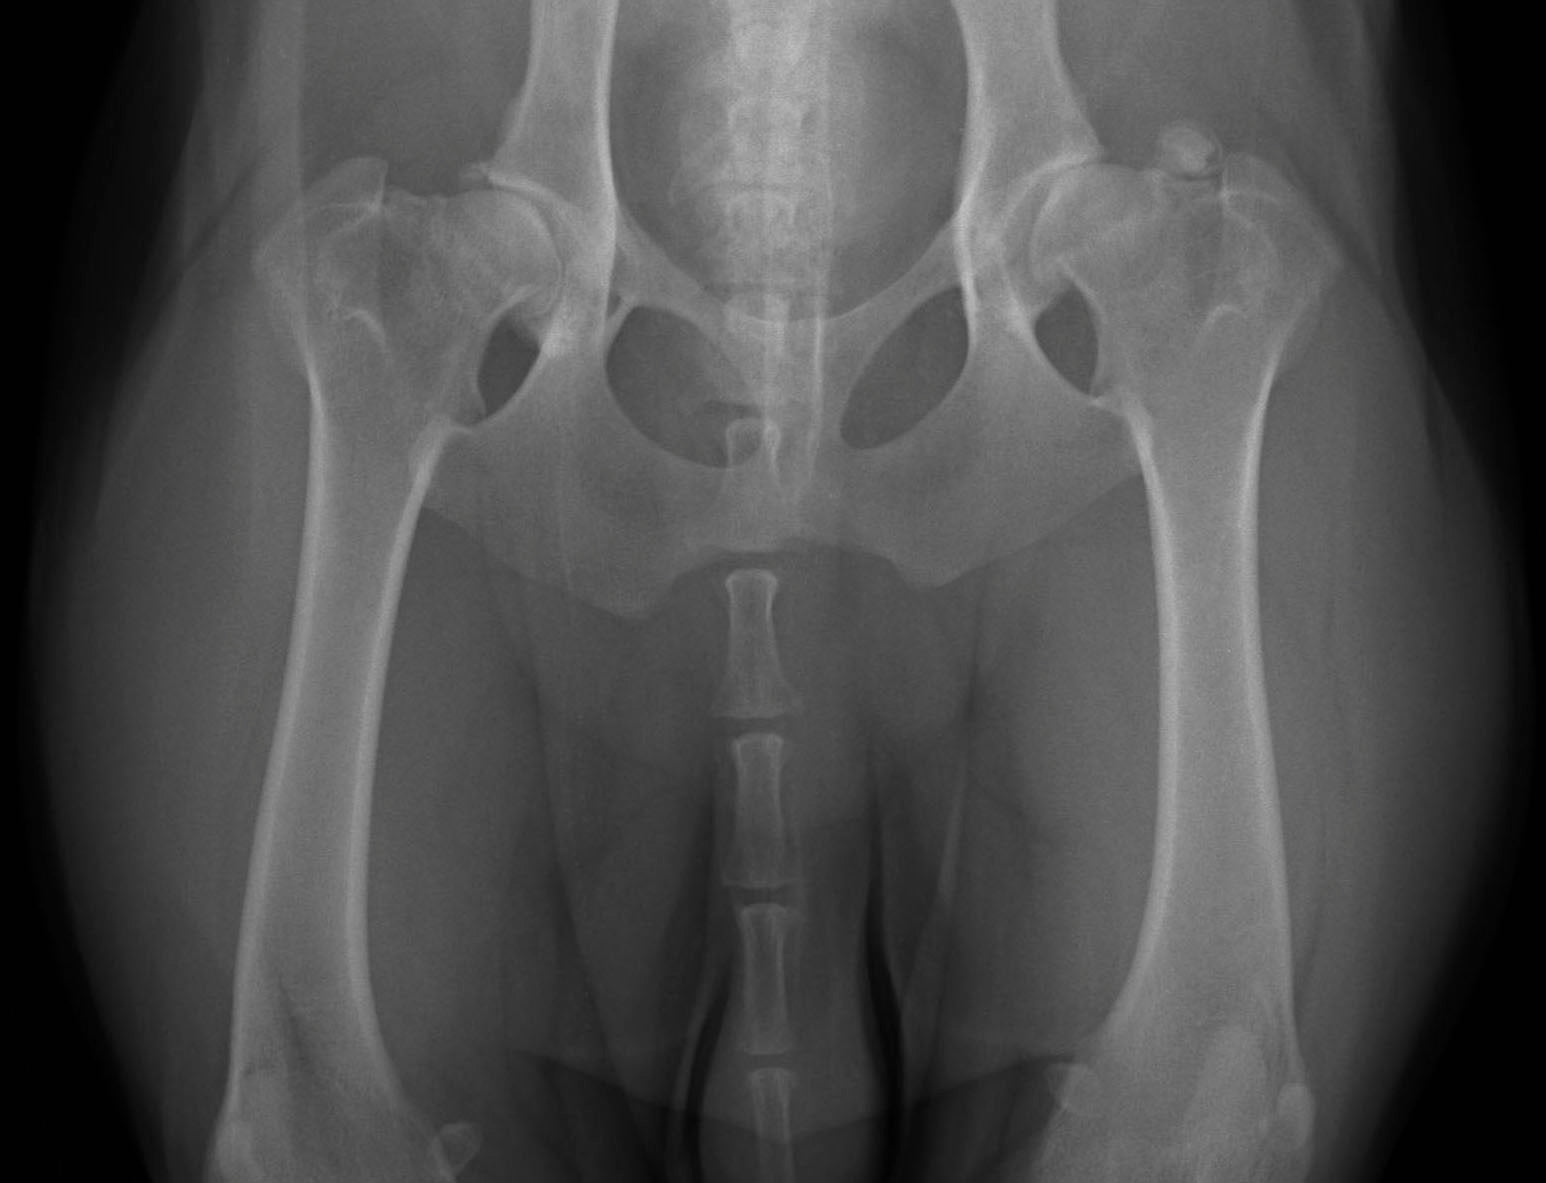

You just found out your dear doggy has been diagnosed with Hip dysplasia. You turn to the internet only to discover there is a lot of misinformation and not a lot of answers. Also known as Canine Hip Dysplasia (CHD), this disease occurs when a dog’s hips do not develop normally and the ball does not fit snugly into the socket, creating stress on the joint. The hip joint consists of a “ball” on the femoral bone, and a “socket” on the hip bone. Joint instability develops, causing damage to the cartilage, gradual destruction of the joint, pain and swelling.